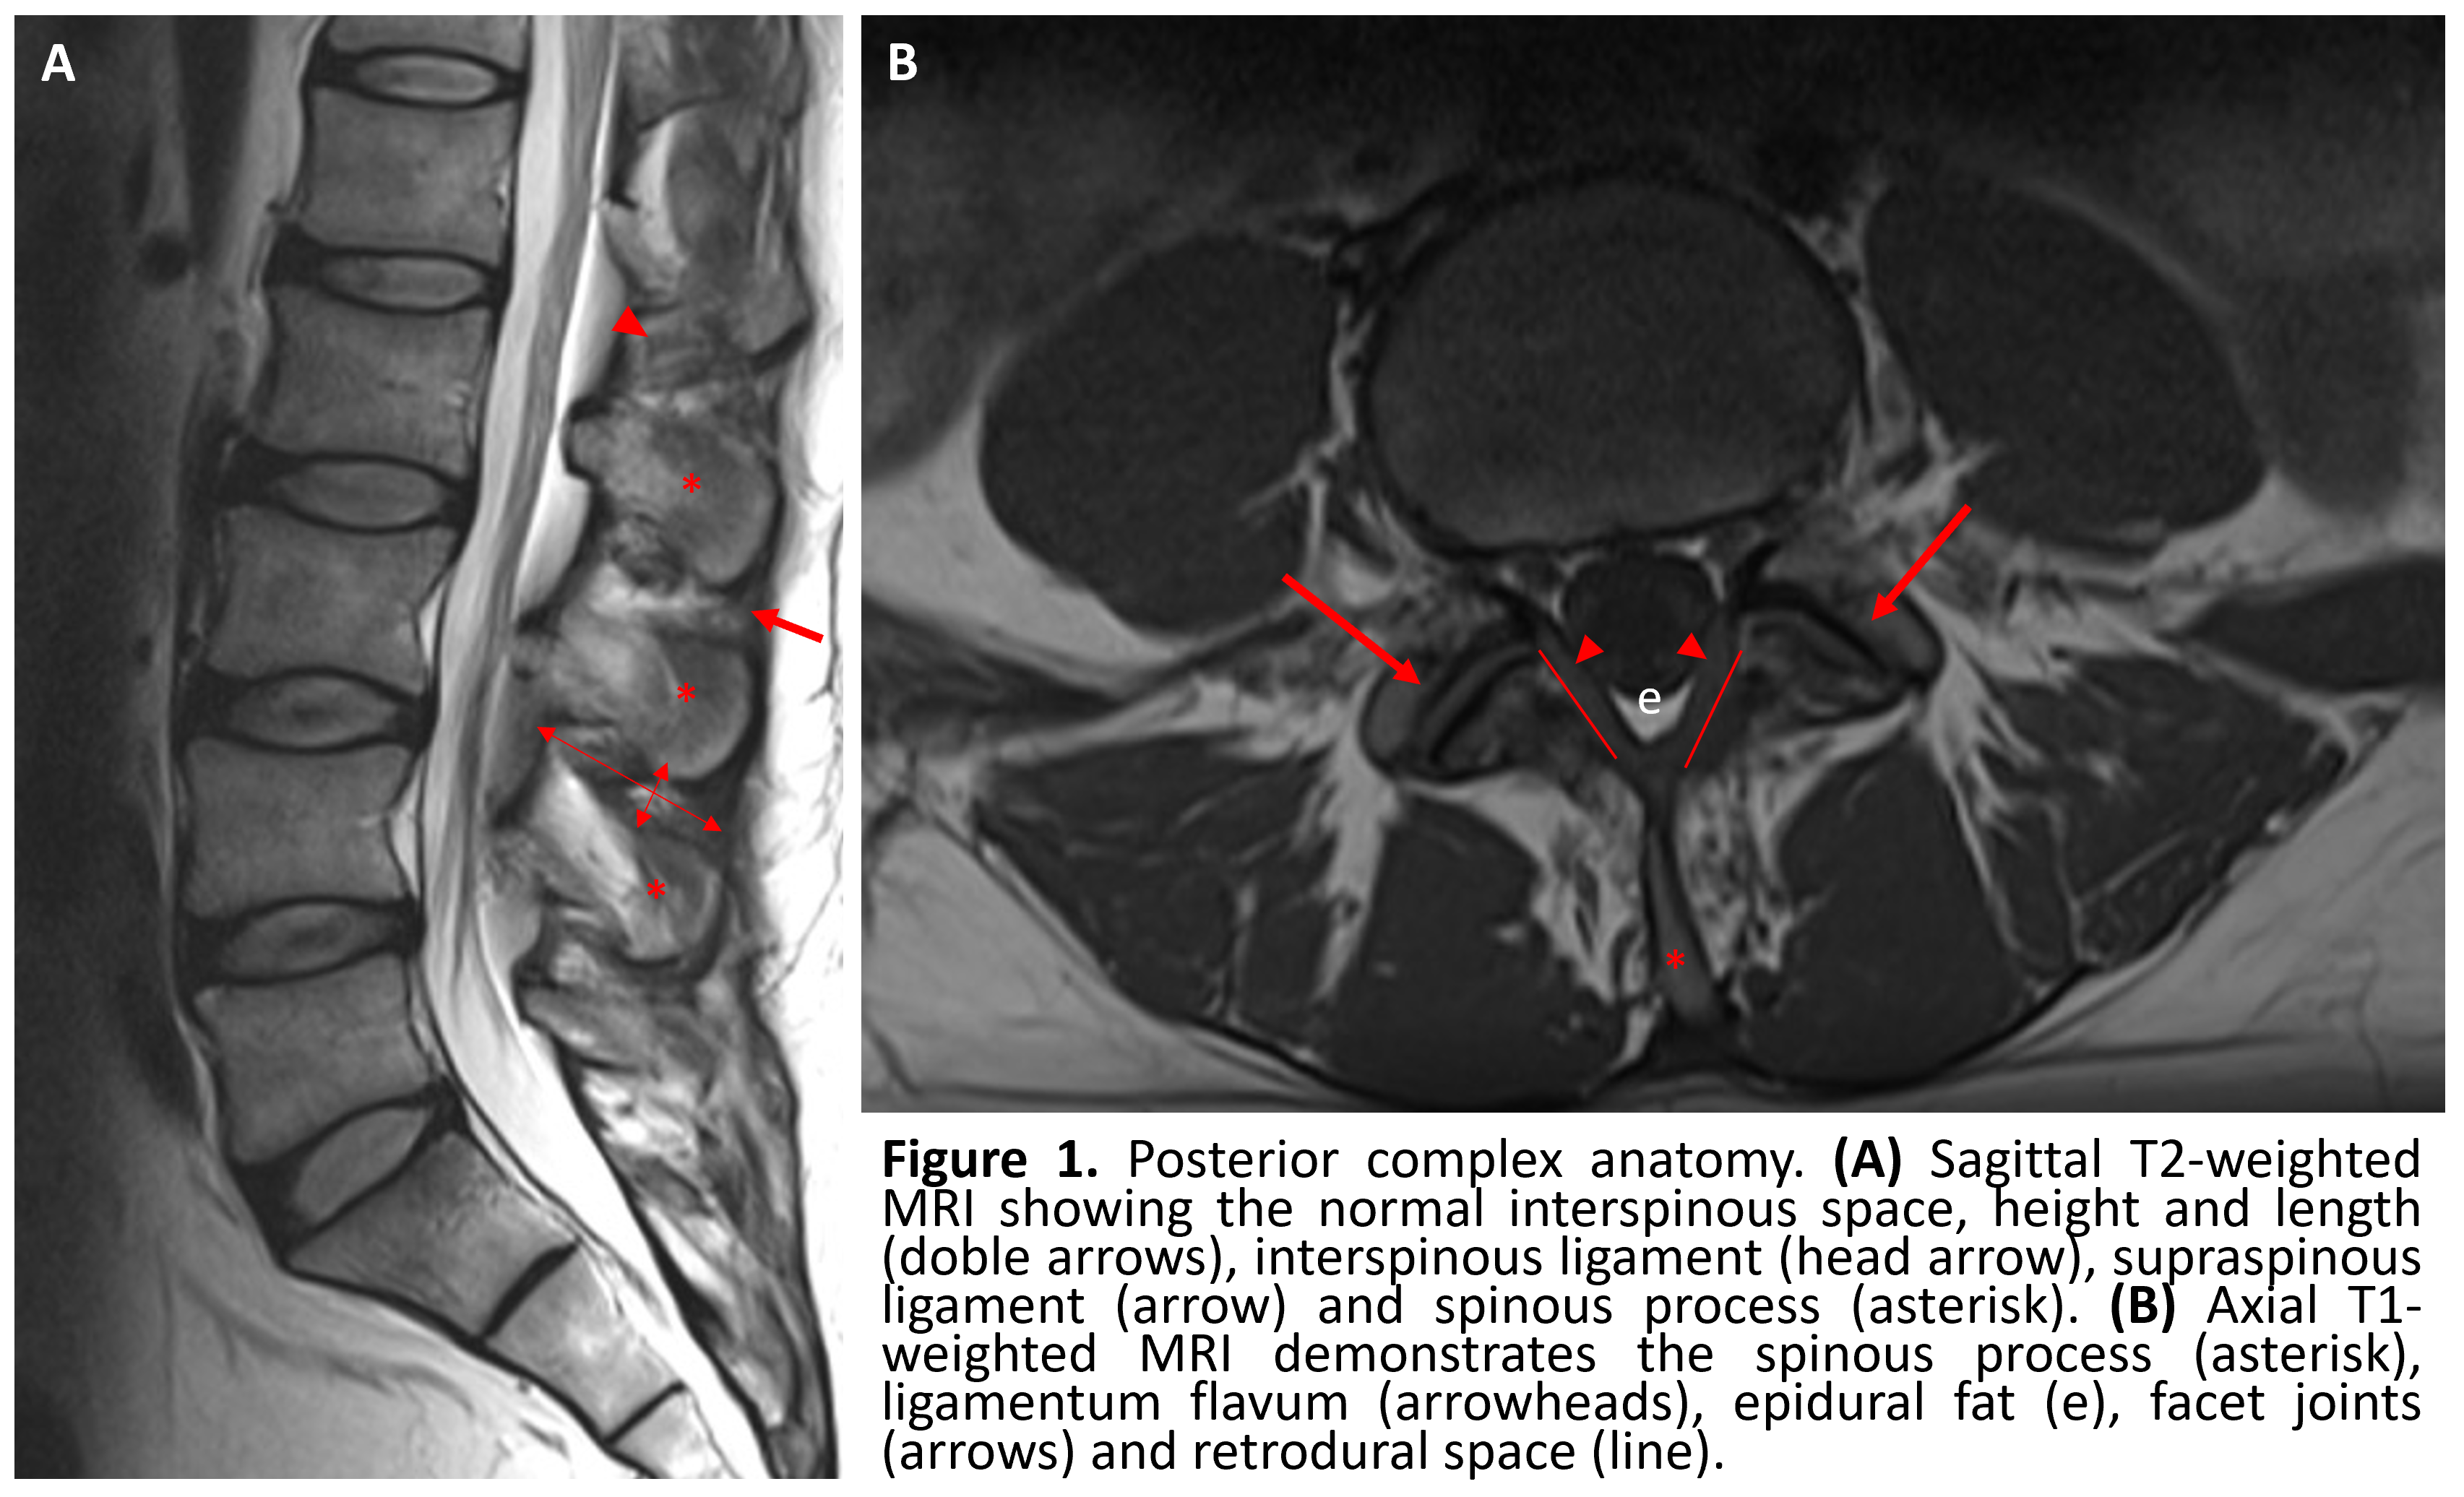

The posterior ligamentous complex inflammatory syndrome: spread of fluid and inflammation in the retrodural space of Okada - Clinical Radiology

The posterior ligamentous complex inflammatory syndrome: spread of fluid and inflammation in the retrodural space of Okada - Clinical Radiology